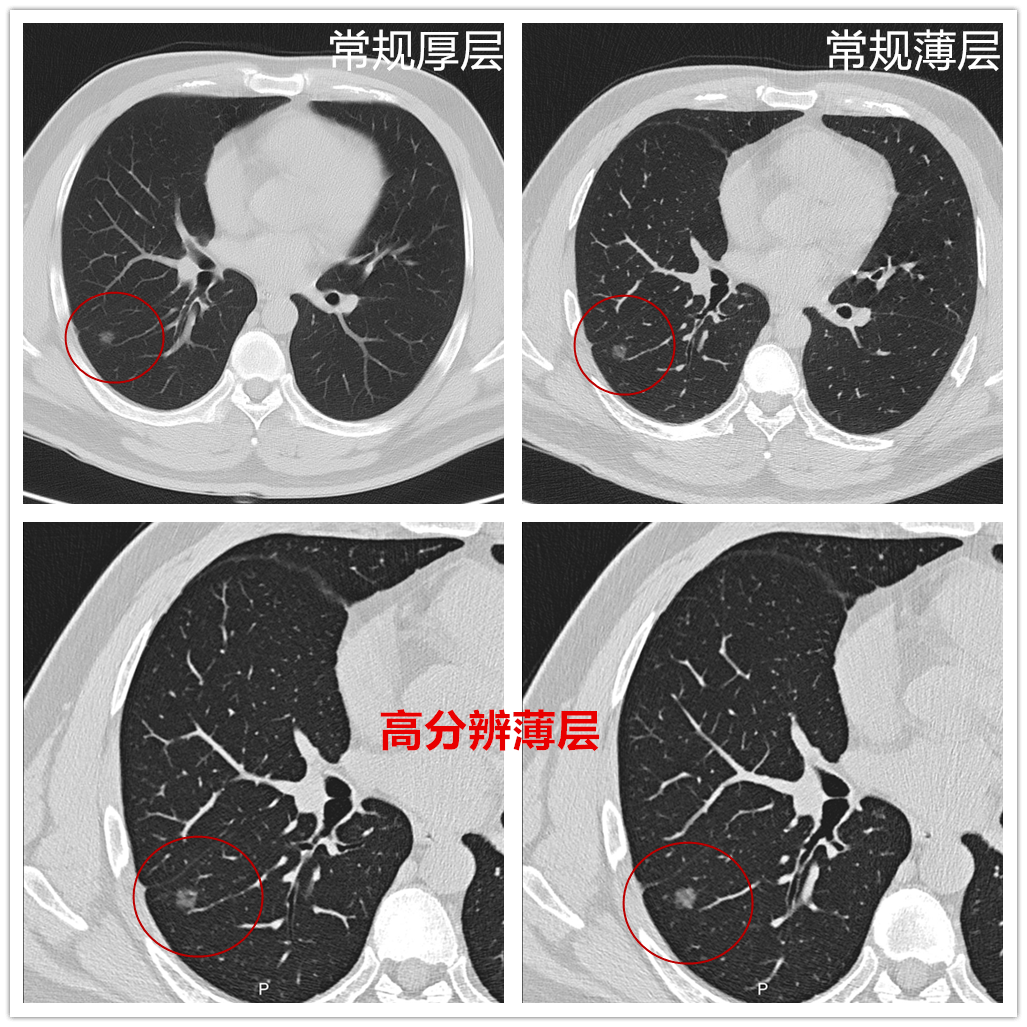

01 獨有的超高清成像技術 “磨玻璃”肺結節不再模模糊糊

Ingenuity為診斷醫生提供1024*1024“顯微”成像,4倍于常規CT的影像解剖細節信息,100萬像素影像鏈實現超高分辨力,可對肺結節、細小病灶、細小結構進行準確顯示和分析評估,減少誤診漏診,提升腫瘤篩查能力及鑒別診斷精確性。

“磨玻璃”肺結節

隨著胸部CT篩查的普及,肺部磨玻璃結節的檢出率也明顯增高,有研究證實95%在體檢中發現的肺癌,在CT影像上表現為 磨玻璃結節。

國科大腫瘤醫院放射科江海濤副主任介紹,專家門診中因肺結節就診的患者比例非常高,嚴重影響人的身心健康。判斷結節是否為磨玻璃密度結節對掃描儀器和檢查技術有著一定的要求和規范。磨玻璃肺結節性質判斷影響臨床決策,要求規范化檢查及精細掃描及重建方式,這臺Ingenuity Core CT實現了肺結節細節方面的高清顯示,特別是其獨有的超高清1024靶掃描對結節細節顯示更多、更清晰、準確,結合我院多年早癌篩查的豐富診斷經驗,可進一步提高肺結節良惡性診斷準確性,而且其硬件性能的提升有效降低了輻射帶來的危害。